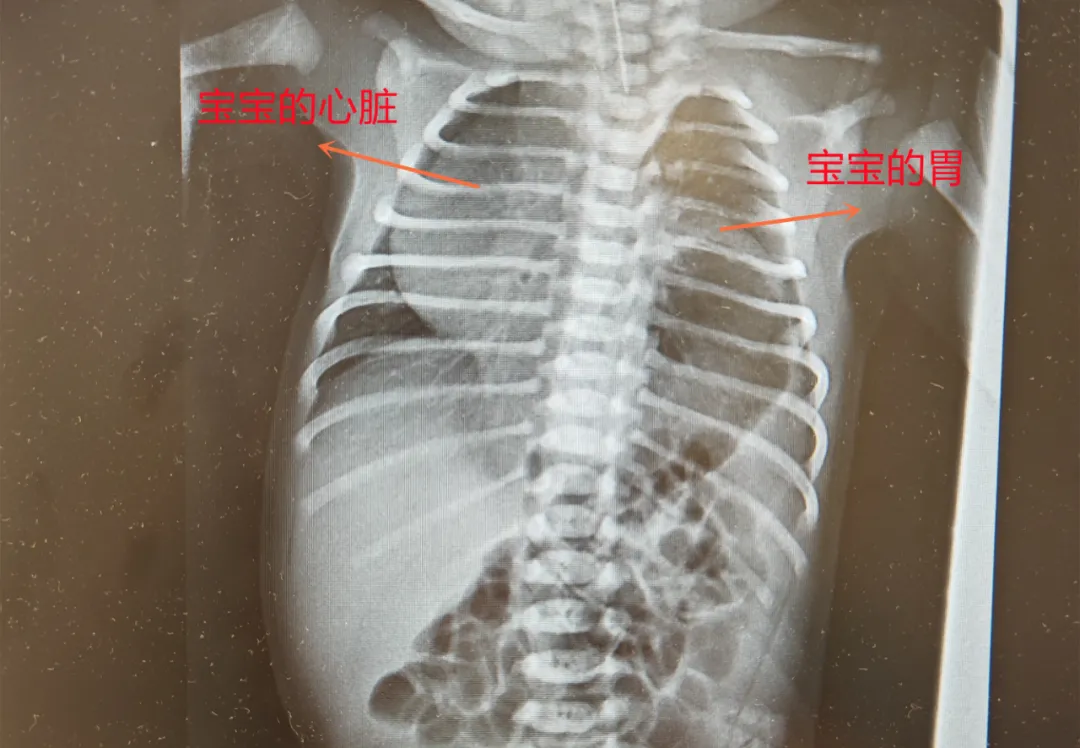

30岁的J女士在大排畸时,被告知胎儿或患左侧膈疝,心脏、胃等器官“错位”,恐致严重肺发育不良、肺动脉高压,甚至胎死宫内,她与家人陷入焦虑。

危急时刻,J女士求助妇产科医院。医院迅速启动多学科协作机制,由主任医师张斌牵头,联合产科、新生儿科、超声科专家,并特邀儿科医院专家会诊。评估后判定胎儿为中危膈疝,羊水正常,若孕期维持肺部发育稳定,足月分娩后经特殊处理与手术,孩子有正常成长机会,这让J女士一家重拾信心。

此后孕期,每次产检都是“闯关”。孕26周至38周,医院为J女士安排高频次高危超声监测,追踪胎儿O/ELHR(评估肺部发育关键指标)及胸腔积液情况。幸运的是,多次检查显示胎儿无水肿、无心包积液,肺头比持续≥45%,器官发育良好,为后续诊疗奠定基础。

孕38周,J女士突发宫缩,产科副主任医师沈婕团队立即启动应急预案,顺利实施剖宫产。同时,新生儿科团队开展子宫外产时处理(EXIT),在胎儿未脱离母体、靠胎盘供血时快速完成气管插管,保障宝宝出生后能自主呼吸。随后,儿科医院儿外科团队接力实施膈疝修补术。经多学科团队无缝协作与照料,宝宝术后恢复顺利,平安出院。这场跨越数月的生命守护,最终以圆满结局落下帷幕。